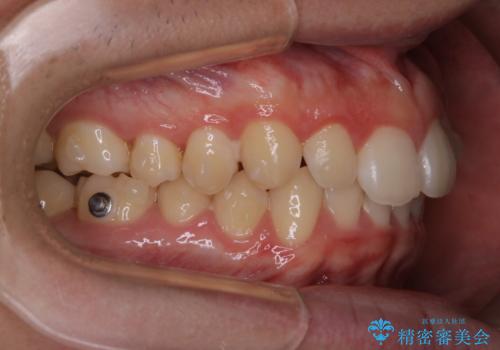

- 上の前歯が見えすぎて気になるとご相談にいらした方です。インビザラインにて前歯の圧下を行うことで歯の見え方の改善し、同時に奥歯の噛み合わせも改善を行いました。

インビザラインを正しく使用して頂けたおかげで、比較的難しいとされる歯の圧下も補助装置を使用せずに行うことが出来ました。上の前歯のラインが整ったことで笑った時の口元の印象を改善させることができ、大変喜んでいただけました。